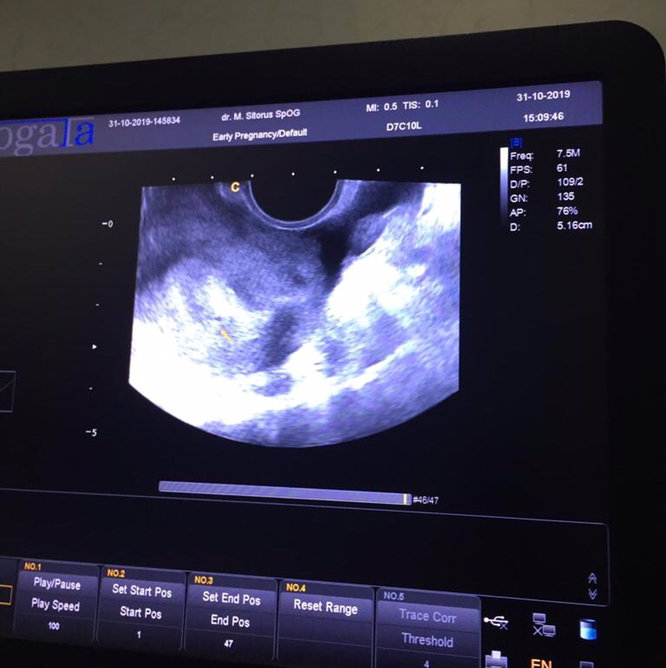

USG TRANSVAGINAL TELAT SEMINGGUAN

Halooo bunda2 mau tanya.. saya sudah telat haid lebih kurang 8 hari. Akhirnya di hari ke 10 telat, saya dan suami memutuskan untuk USG TransVaginal. Namun hasilnya ini bunda2. Kata dokter belum jelas tanda2 kehamilan. Tapi ada lingkaran kecil yg belum jelas apa itu, di zoom ya bun ada tanda panah warna kuningnya menunjukkan lingkaran kecilnya.. Ada yg punya pengalaman yang sama dengan saya gak bun ? Di cek lagi sebulan atau 2 bulan kemudian..

mungkin itu baru kelihatan kantongnya bun, saya waktu pertama usg juga baru keliatan kantongnya aja bun, itu pas usia 6w.